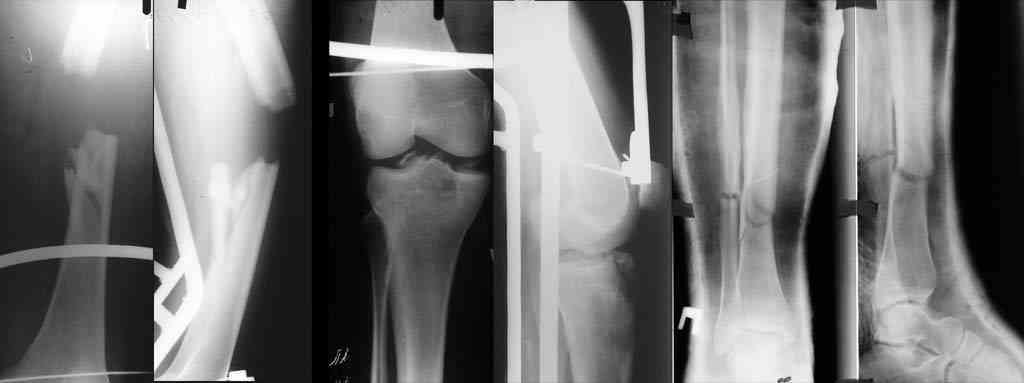

К сожалению, отправить все снимки и КТ сразу не получилось. Дополняю.